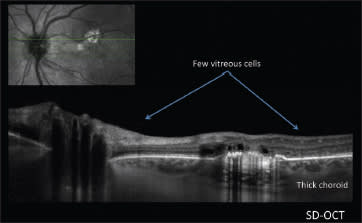

The second case Dr. Freund presented also used ultra widefield FA. This patient, a 55-year-old white woman, presented with what appeared to be posterior vitreous detachment–related symptoms, including the sudden onset of floaters related to a vitreous hemorrhage (Figure 1). The ultra widefield FA revealed instead that the problem arose from neovascularization related to peripheral nonperfusion; the fellow eye showed the same problem (Figures 2 and 3).

Figure 1. In this 55-year-old white woman, there was the appearance of a vitreous hemorrhage.